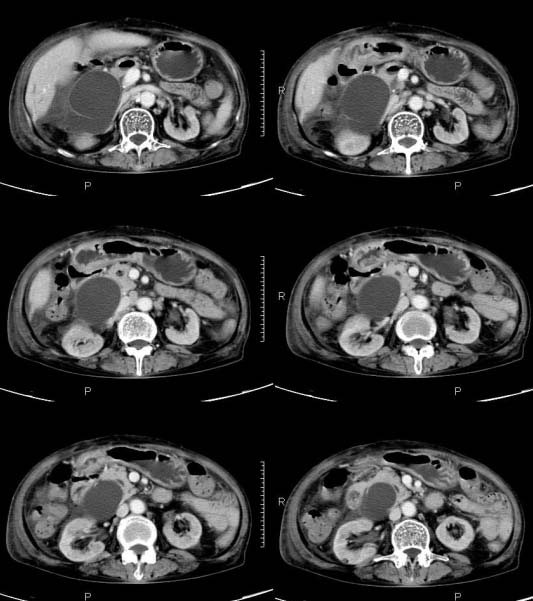

女,71岁,腹痛、腹胀、黄疸20余天,b超示肝内外胆管高度扩张内伴絮状物质(未提示梗阻部位或结石影),经抗炎解痉治疗后,肝功能有所好转,但胆道梗阻状态并未减轻。患者曾于1970年代做过胆囊切除术,1997年因胰腺炎而手术;且患者有糖尿病10余年。ct图片传了静脉期,未传动脉期了,最后一序列为3.2mm薄扫,请各位同仁仔细看看,确定一下胆管梗阻的部位,是炎性梗阻还是肿瘤性梗阻,是否与胰腺炎有关系,扩张胆总管中段前缘是否是胰管。请高手们最好用图示来指出梗阻部位。

扩张的胆管直达胰头,但胰头增大又不明显,且无异常密度影。考虑壶腹部占位。

请大家看看扩张的胆总管内见一弧线形间隔,怎样解释?

肝内外胆管显著扩张,考虑先天性胆管囊肿(ⅳ型)。

肝内胆管远侧、近侧不比例扩张,以近侧为明显。胆总管扩张。考虑先天性胆管囊肿(ⅳ型)。